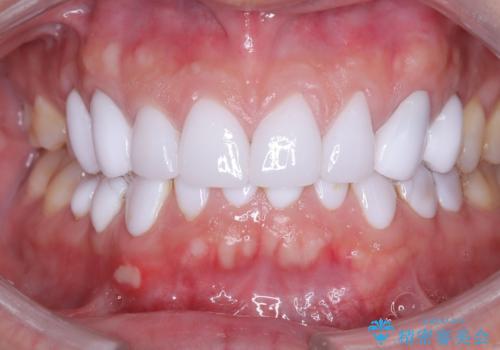

前歯のデコボコと開口を改善し、美しい口元へ